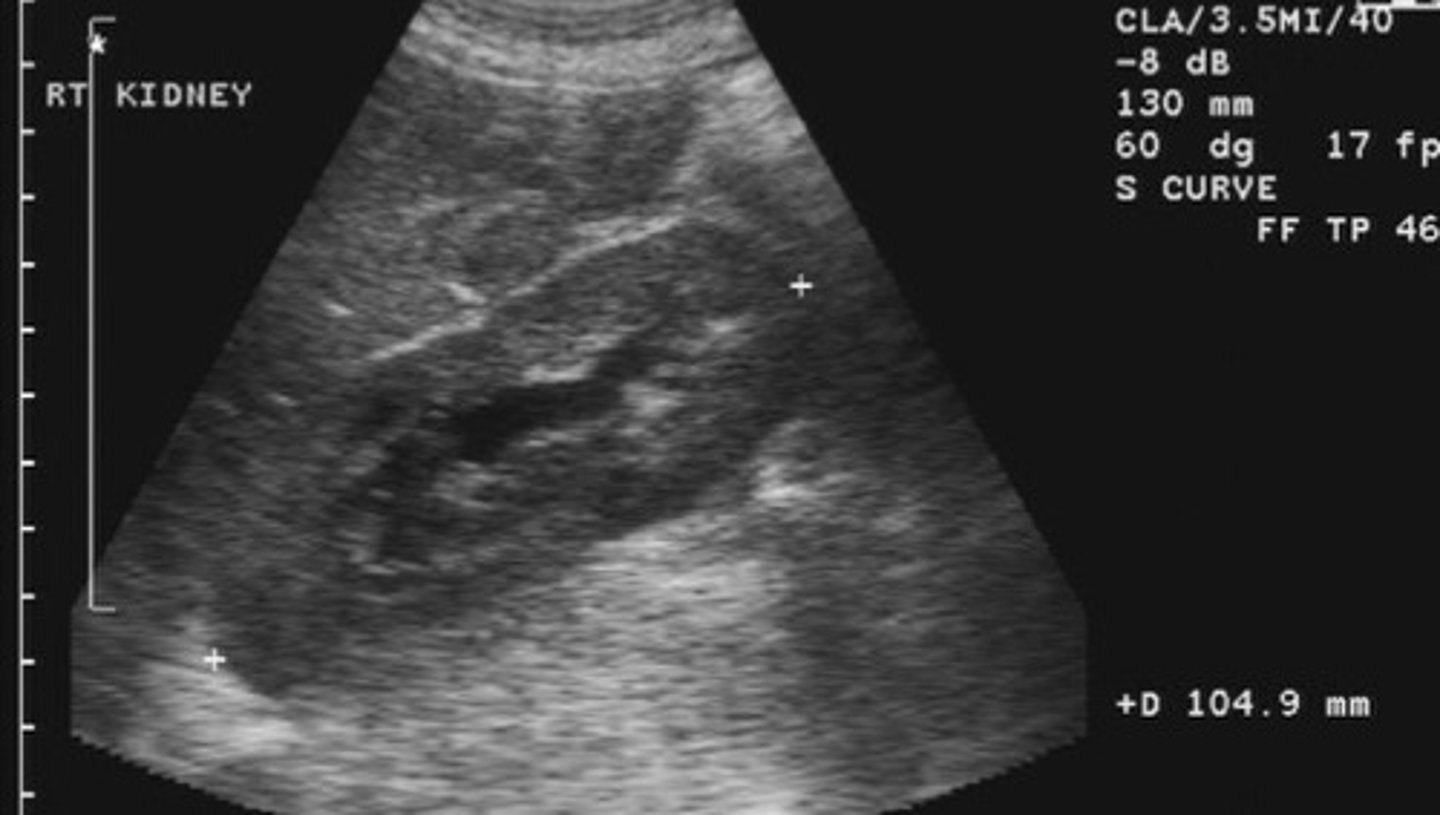

Nephrolithiasis

What does this image show

<p>What does this image show</p>

Echogenic focus or foci with posterior shadowing

Describe the sonographic appearance of nephrolithiasis